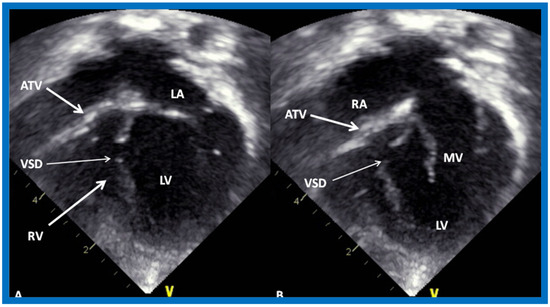

Figure 17.

Selected video frames from apical four-chamber, 2-dimensional echocardiographic views of a neonate with tricuspid atresia showing an enlarged left ventricle (LV), a small right ventricle (RV) and a dense band of echoes at the site where the tricuspid valve echo should be (ATV) (thick arrow) with closed (A) and open (B) mitral valve. A moderate sized ventricular septal defect (VSD) (thin arrows) is shown. LA, Left atrium; RA, Right atrium. Reproduced from Rao P.S. [39].